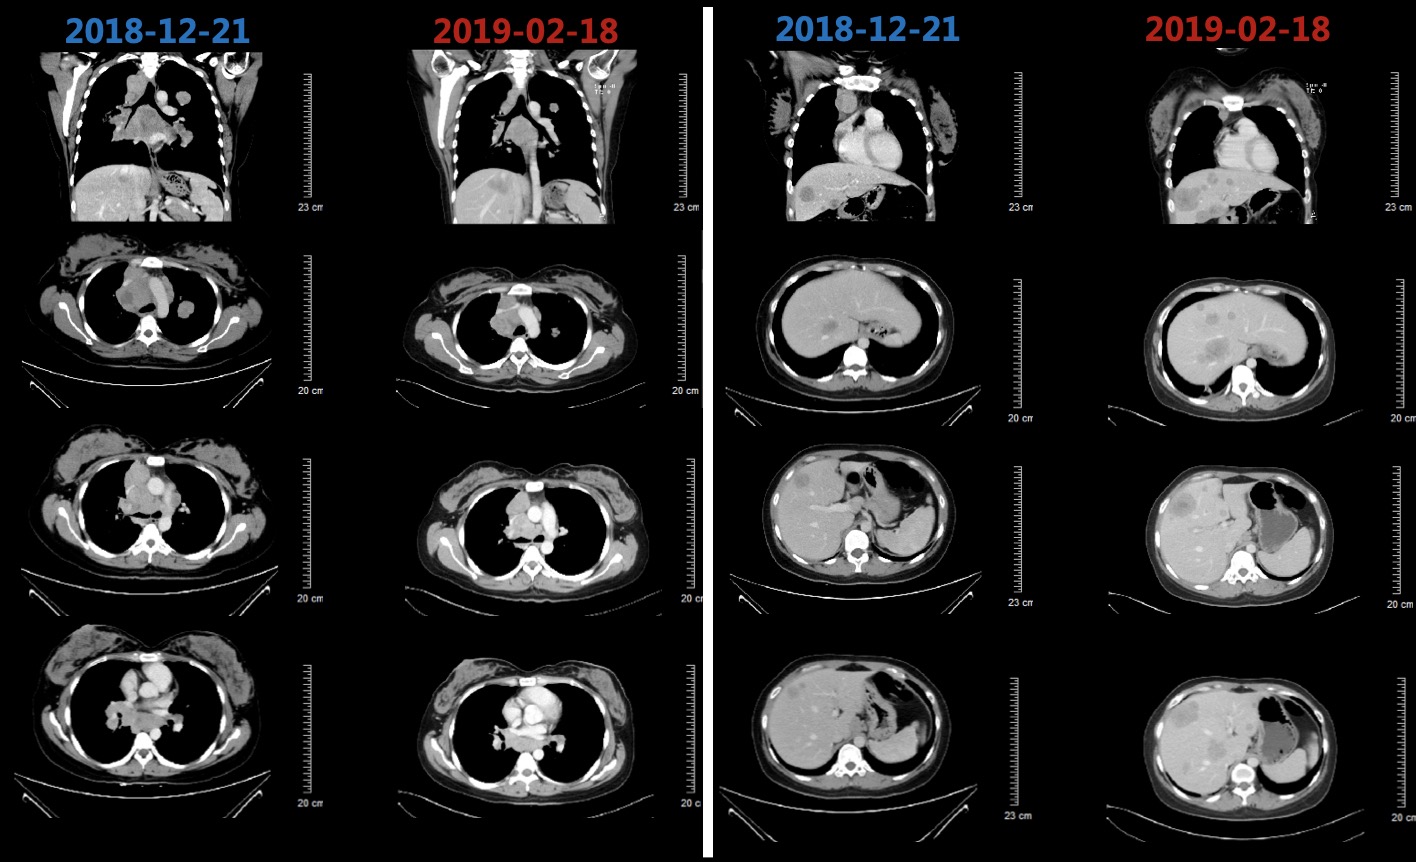

患者于2018-12-26、2019-01-19分别行第1-2周期TC方案(紫杉醇脂质体+卡铂,每3周1次),患者基线和化疗后肿瘤标志物变化如图3所示,肺和肝脏病灶变化影像如图4所示,2019-02-18复查CT提示肺部病灶稳定(缩小),肝脏病灶增多增大,总体疗效评价疾病进展(PD)。

图4 患者基线和化疗后肺部病灶和肝脏病灶对比影像,肺部病灶缩小,肝脏病灶增多增大

2019-02-19、2019-03-14行二线贝伐珠单抗+多西他赛化疗(贝伐珠单抗+多西他赛,每3周1次)。2019-03患者开始出现腰部疼痛,考虑为L1椎体骨转移导致,2019-03-19开始行腰骶部局部放疗,2019-04-04复查CT结果如图5所示,肺部病灶稳定(部分缩小),肝脏病灶增多增大、T9-T12椎体新发转移瘤,总体疗效评价(PD)。

图5 2019-04-04复查胸腹部CT结果影像,结果显示肺部病灶稳定(部分缩小),肝脏病灶增多增大、T9-T12椎体新发转移瘤